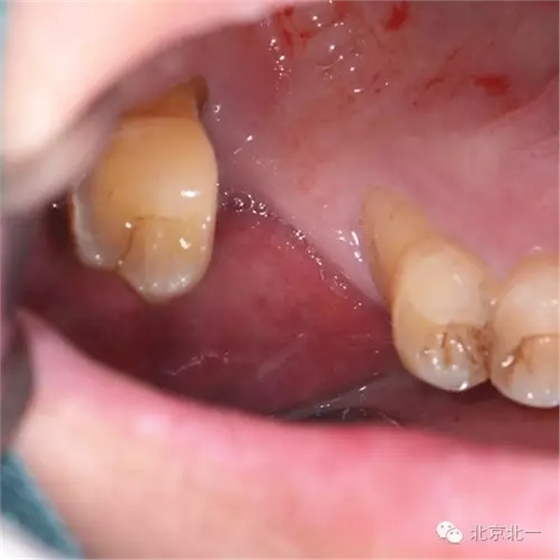

患者,男,30歲,右側上頜后牙區(qū)缺失,咨詢種植。

檢查:15、16 缺失。17三度松動。

圖一:手術前臨床照片